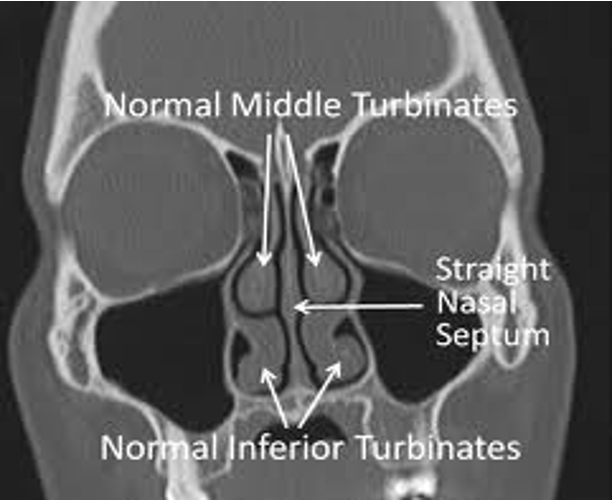

Turbinate Hypertrophy